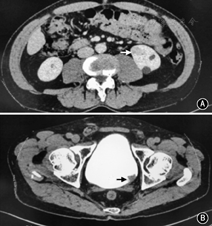

共有24例患者纳入本研究,患者中位年龄是69.5岁(48~79岁)。19例男(79.2%),5例为女(20.8%)。10例(41.7%)有吸烟史。主要症状是肉眼血尿14例(58.3%);10例患者是无症状的,通过体检发现肿瘤。经过B超,CT和膀胱镜等检查,21例患者术前诊断为肾癌并发尿路上皮癌,2例术前仅诊断为肾癌,1例术前仅诊断为输尿管癌。肾癌+上尿路尿路上皮癌7例(29.2%),肾癌+膀胱癌15例(62.5%),肾癌+上尿路尿路上皮癌+膀胱癌2例(8.3%),肿瘤平均直径3.3(0.6~8)cm,有2例远处转移。1例典型的肾癌并发同侧肾盂癌患者的CT见图1;图2显示了1例肾癌并发膀胱癌患者的CT表现。